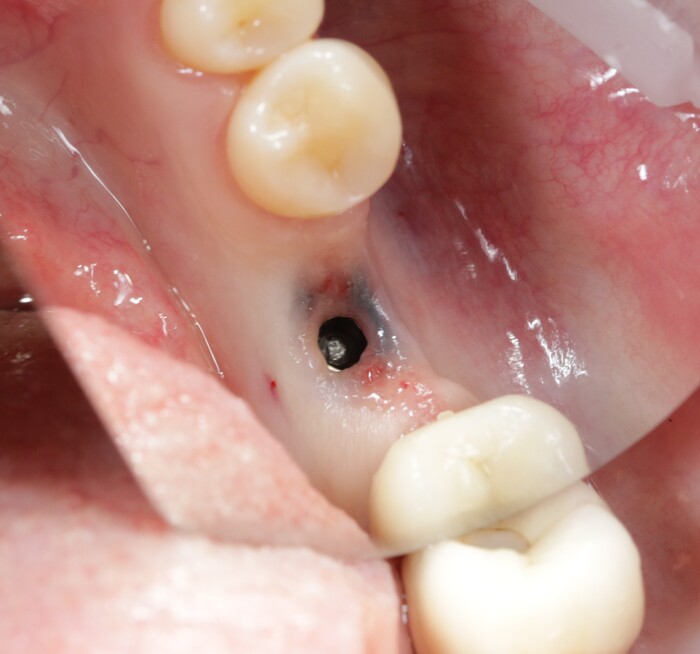

Часть с резьбой осталась в имплантате

На рентгеновском снимке:

Внутренний конструктив имплантата:

Благо я работаю с профессионалами. Иван Алгазин, наш ортопед, умудрился достать обломок винта, что крайне сложно сделать не повредив принимающую часть в имлпантате:

На фото ниже виден шестигранник, обратите внимание какой он шероховатый. Он должен быть отполированным, гладким. (К слову, о той микроподвижности, про которую я говорил выше)